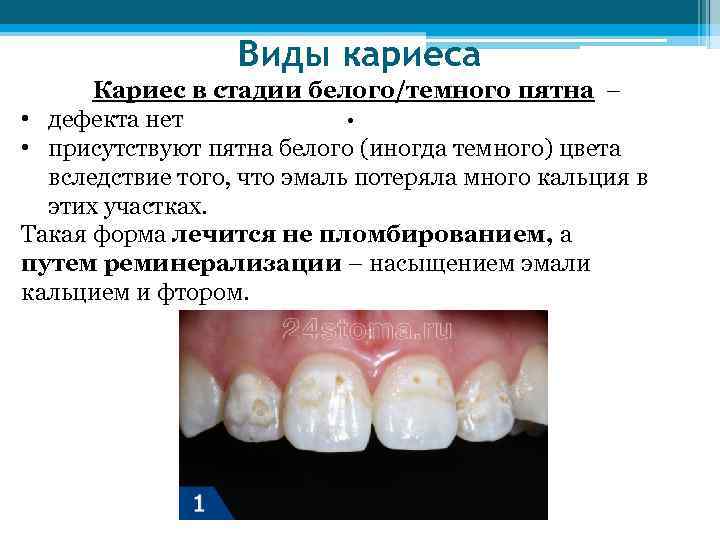

Виды кариеса Кариес в стадии белого/темного пятна – • • дефекта нет • присутствуют пятна белого (иногда темного) цвета вследствие того, что эмаль потеряла много кальция в этих участках. Такая форма лечится не пломбированием, а путем реминерализации – насыщением эмали кальцием и фтором.

Виды кариеса Кариес в стадии белого/темного пятна – • • дефекта нет • присутствуют пятна белого (иногда темного) цвета вследствие того, что эмаль потеряла много кальция в этих участках. Такая форма лечится не пломбированием, а путем реминерализации – насыщением эмали кальцием и фтором.